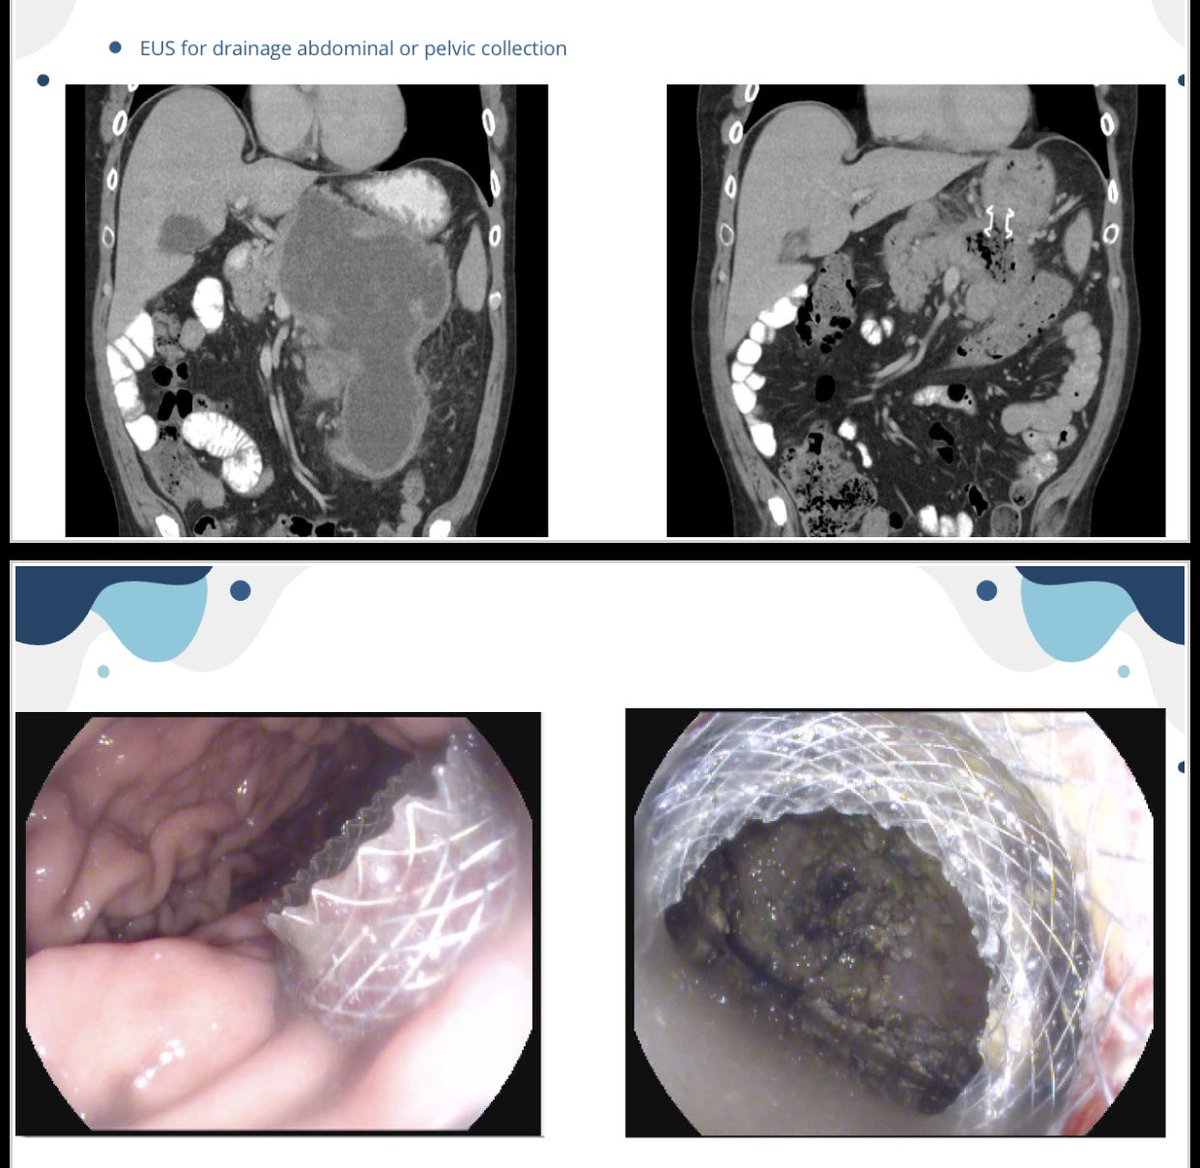

تسخدم في ازالة السوائل المتجمعة بسبب التهاب البنكرياس او الصديد في اعلى البطن بدل العملية